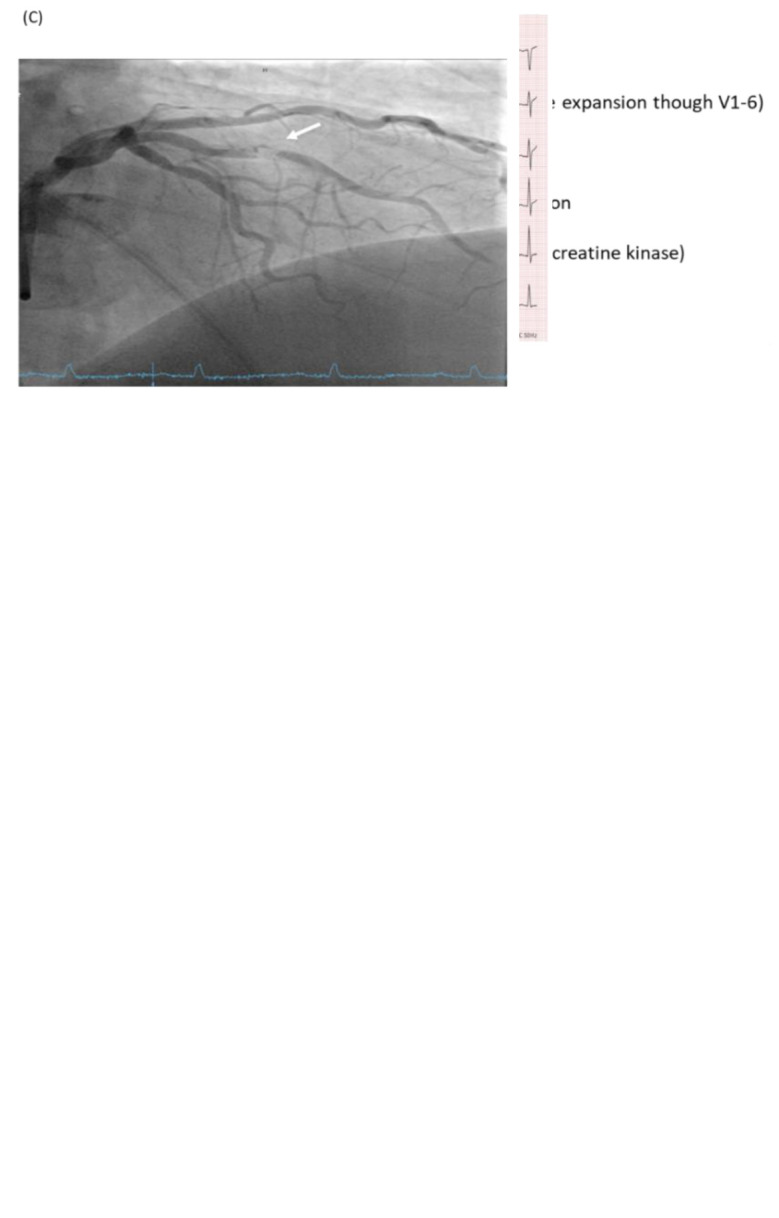

This report presents the case of a 61-year-old patient who experienced sporadically occurring episodes of chest pain lasting approximately 15 minutes. The initial electrocardiogram (ECG) showed unspecific repolarization disturbances but no ST-elevation indicative of ST-elevation myocardial infarction (STEMI). However, upon closer examination, biphasic T waves were detected, suggestive of specific repolarization abnormalities. The conventional Wellens criteria were met, possibly indicating an etiopathogenetic correlation with the patient's complaints. Subsequent coronary angiography revealed a functional occlusion of the middle segment of the left anterior descending artery, which was treated by percutaneous transluminal coronary angioplasty/drug eluting stent. It also revealed a severely stenosed distal circumflex artery, indicating a two-vessel coronary disease. If we had used only conventional STEMI criteria, this patient would have certainly been missed. Therefore, when evaluating patients presenting with chest pain, it is imperative to consider non-occlusion infarction ECG abnormalities, known as STEMI equivalents. This case, moreover, highlights the importance of the non-officially proposed occlusion myocardial infarction (OMI)/non-OMI paradigm instead of the old STEMI/non-STEMI dichotomy.